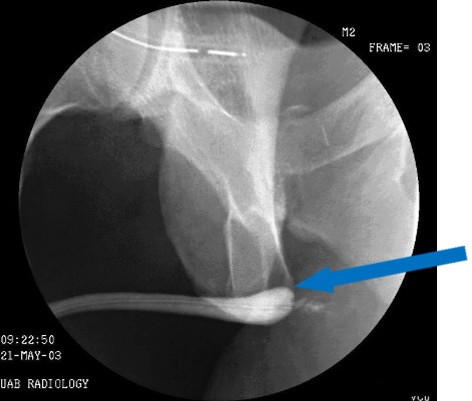

Ο συνδυασμός ανιούσας (Εικόνα 1) και κατιούσας (Εικόνα 2) ουρηθρογραφίας αναδεικνύει αναστομωτικό στένωμα μήκους ενός εκατοστού. Η προσπάθεια καθετηριασμού με καθετήρα 10 French, ώστε να ακολουθήσει διαστολή του στενώματος αποτυγχάνει.

Εικόνα 2 Κατιούσα ουρηθρογραφία (Το μπλέ βέλος δείχνει το σημείο του στενώματος)